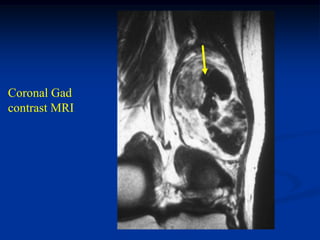

Case #1199

30 year male with

myxoid liposarcoma

posterior thigh

Sagittal T-1 MRI

Sagittal T-2 MRI

tumor

Axial T-1 MRI

Axial Gad contrast MRI

Coronal Gad

contrast MRI